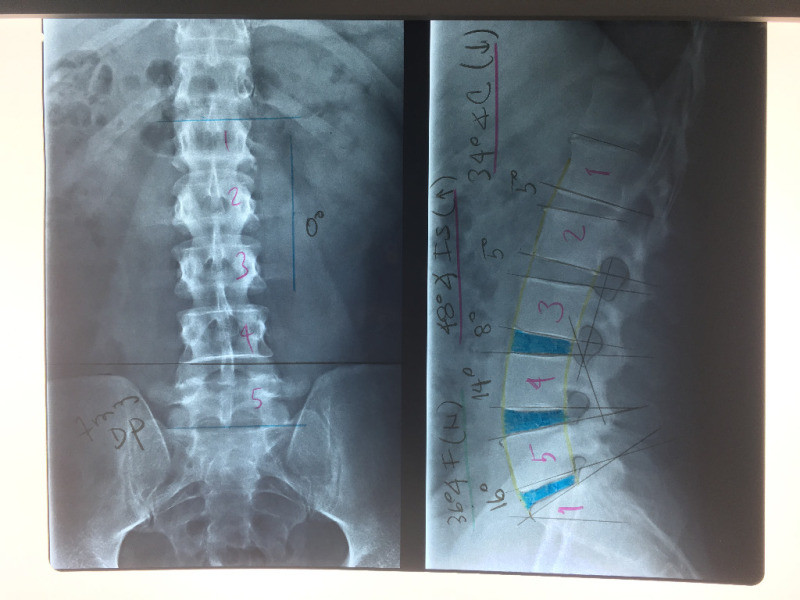

Cirugía de columna de mínima invasión

Envíado por Dr. Hugo Enrique Castro Cordero